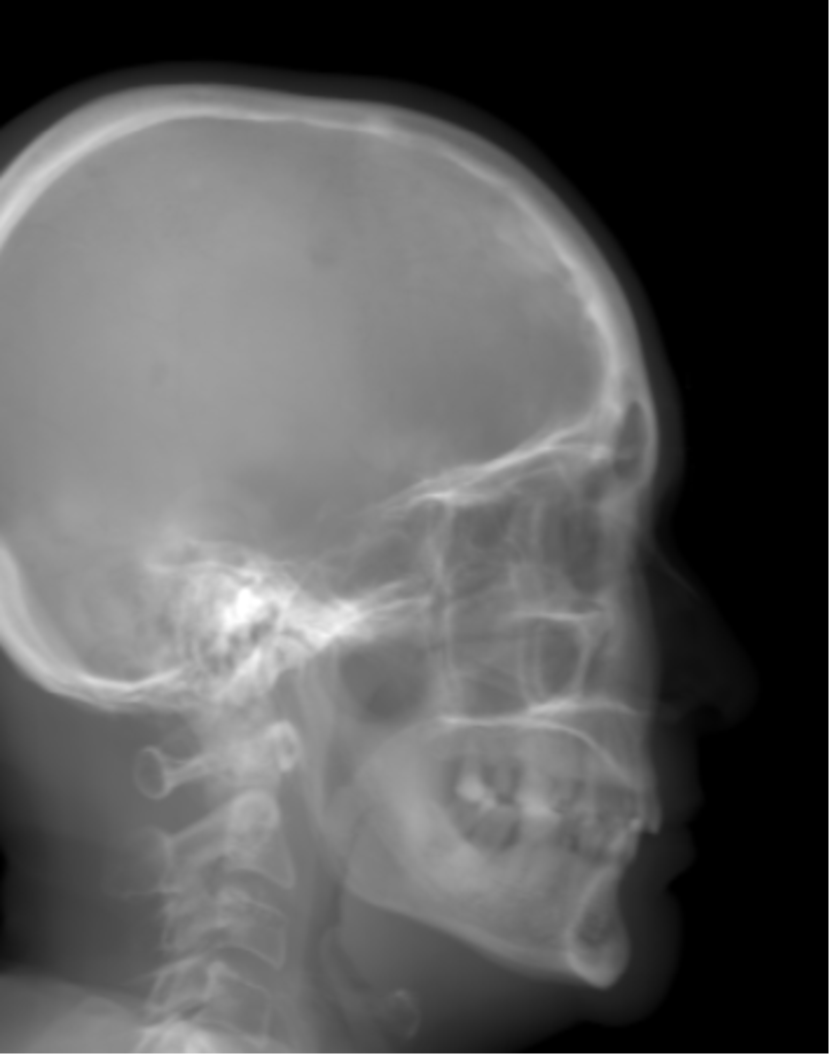

Refer to caption

(a) Real cephalogram

(b) Synthetic cephalogram

(c) Plot of samples and sigmoid curves

Fig. 2: Image contrast difference between real conventional cephalograms and RayCast synthetic cephalograms: (a) a real cephalogram example; (b) a RayCast synthetic cephalogram example; (c) the plot of samples between RayCast synthetic cephalograms and real cephalograms with an original sigmoid curve (red) and our proposed modified sigmoid curve (blue).

In Fig. 2, one real conventional cephalogram example and one example of 𝒈𝒈\boldsymbol{g} are displayed, where evident image contrast difference between these two images is observed. It is because the X-ray films used in conventional cephalograms have the special nonlinear optical property that the characteristic curve between optical density and logarithmized X-ray exposure has a sigmoid-like shape [42]. According to the Lambert-Beer law, the logarithmized X-ray exposure is equivalent to the attenuation integral. It indicates that the intensity relation between the desired cephalogram and the attenuation integral image 𝒈𝒈\boldsymbol{g} should also exhibit a sigmoid-like curve. Therefore, to make the image contrast of synthetic cephalograms similar to conventional cephalograms, a sigmoid intensity transform is necessary.